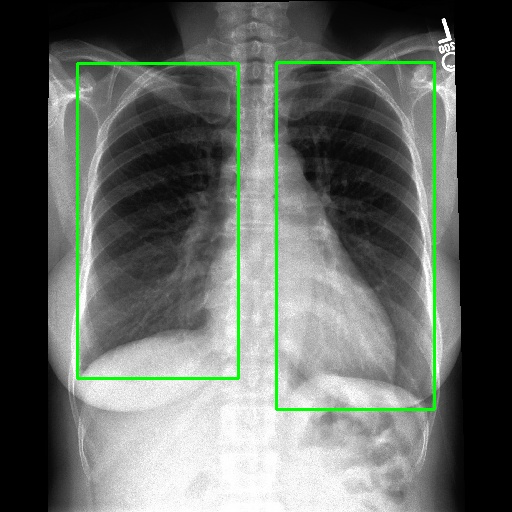

Refer to caption

(a) Example of locating ROI via SAT[29].

(b) Example of locating ROI via BA-Transformer [30].

(c) Example of locating ROI via Chexmask [31].

Figure 6: Example of ROIs and their corresponding textual descriptions.

We employ various strategies to locate Regions of Interest (ROIs) in images. For datasets that already include localization annotations, such as segmentation masks or bounding boxes, we derive the ROIs from these existing annotations. Specifically, bounding boxes are directly used as the ROIs, while segmentation masks are converted to ROIs by creating the smallest bounding box that covers the mask. When such localization annotations are not available, we apply different pretrained expert models listed in the Appendix to generate ROIs. For text-prompt driven grounding model[29], we use disease and organ information in coarse captions as text prompts to guide the model in segmenting specific parts. Examples of generated ROIs from various modalities with different models are demonstrated in Figure 6. It is important to note that for modalities such as X-ray and MRI scans viewed from the z-axis, our ROI localization employs a coordinate system relative to the human body, resulting in a left-right reversal in the image representation.

Without ROIs, the original description is limited to a brief global analysis of the image. However, with ROIs, MLLMs  can perform a more detailed local analysis of the ROIs and assess the impact of lesion ROIs on the surrounding normal regions, as demonstrated in Figure 4.